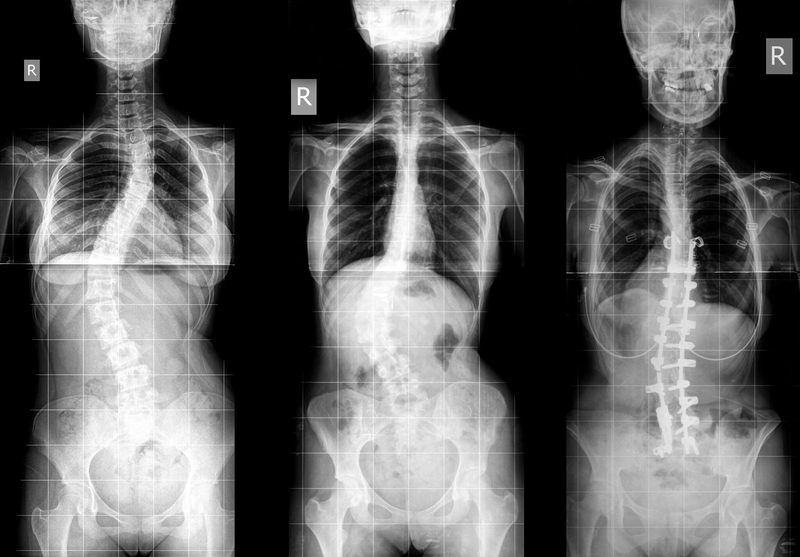

Vẹo cột sống vô căn ở thanh thiếu niên là tình trạng cột sống bị cong bất thường, xuất hiện ở tuổi thơ ấu hoặc thanh thiếu niên. Thay vì phát triển thẳng, cột sống phát triển cong sang hai bên, thường có hình chữ “S” hoặc “C” thon dài; xương cột sống cũng hơi xoắn hoặc xoay. Vẹo cột sống ở thanh thiếu niên xuất hiện trong giai đoạn tăng trưởng nhanh chóng của thanh thiếu niên. Trong nhiều trường hợp, đường cong cột sống bất thường vẫn ổn định, mặc dù ở một số trẻ tình trạng này trở nên nghiêm trọng hơn theo thời gian. Không rõ lý do, những đường cong trầm trọng và tiến triển xảy ra thường xuyên hơn ở bé gái so với bé trai. Tuy nhiên, vẹo cột sống nhẹ cũng phổ biến như nhau ở bé gái và bé trai.

Phân độ vẹo cột sống: